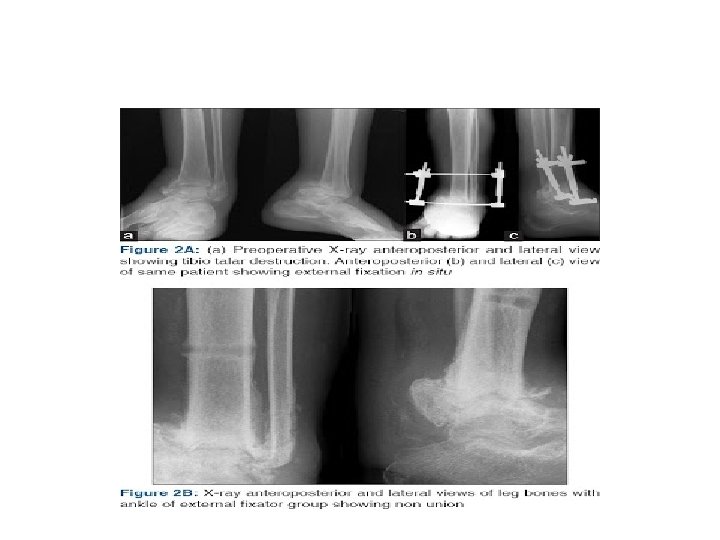

CHARNLEY’S EXTERNAL FIXATOR • COMBINED OPEN SURGICAL DEBRIDEMENT AND APPLICATION OF EXTERNAL FIXATOR • ONE PIN THROUGH THE TIBIA & ONE THROUGH THE NECK OF TALUS WITH CONNECTING BARS BETWEEN THE PINS • INTACT ACHILLES TENDON-TENSION BAND • AFTER 8 WEEK – BEAR WEIGHT • AFTER REMOVAL-IMMOBILIZED IN B/K CAST -4 WEEKS

CALANDRUCCIO EXTERNAL FIXATOR • TRIANGULAR CONFIGURATION-TO ACHIVE STABILITY & COMPRESSION ACROSS TIBIOTALAR JOINT • PINS-THROUGH TIBIA , THE NECK & BODY OF THE TALUS • FUSION SITE-BUTTRESSED WITH BIMALLEOLAR ONLAY BONE GRAFT • DOESN’T REQUIRE INTACT ACHILLES TENDON

COMPLICATIONS • Non-union is the most common complication following ankle arthrodesis • Others include – – Infection Never injury malunion wound problems